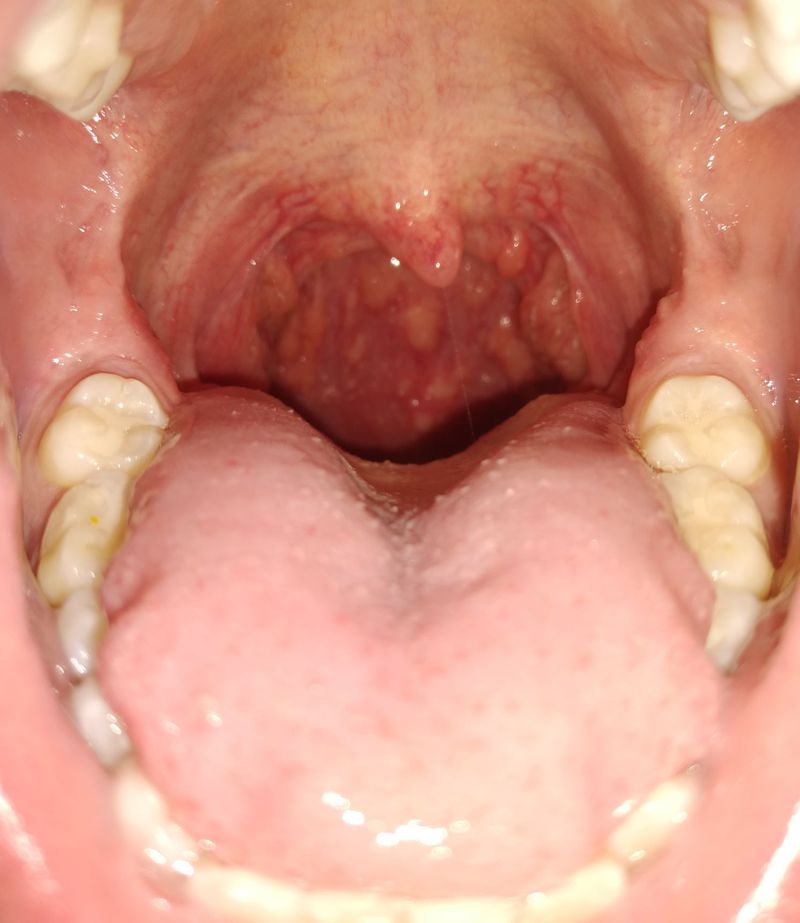

Does anyone know what this could be,  lasting months now

Cobblestone throat ,lymphoid tissue pockets

Cobble stoning? Post nasal drip?